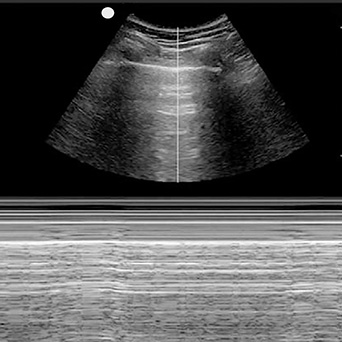

Lung Ultrasound

- Appropriate probe selection, gain, depth, and positioning

- Identification of intercostal morphology

- Pleural sliding

- Recognition of A-lines, B-lines, Z-lines, and lung pulse

- Identification of the diaphragm and subdiaphragmatic structures

- Recognition of pleural effusion

- Thymus (where visible)